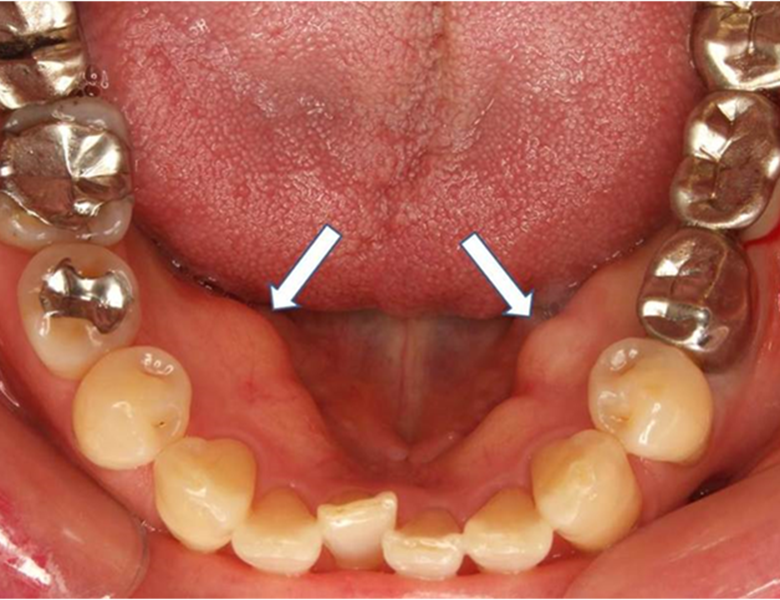

骨隆起(こつりゅうき)

上顎の真ん中や、下の歯の裏側の歯茎にできる、非常に硬い盛り上がりです。

腫瘍ではなく、骨が盛り上がったものです。

噛み締めや食いしばりの強い方によく見られます。

基本的には放っておいても大丈夫ですが、入れ歯が当たって痛む場合は処置を検討します。